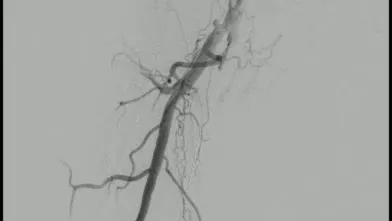

血管内超音波(IVUS)を行うとガイドワイヤーはステントの中心部を通過していたが、予想通り病変内には大量の血栓が堆積していた(動画4)。7 mmのバルーンで拡張したのち、ステント遠位端より2 cm程度離れた遠位の健常部にhealthy landingをとって(動画5)バイアバーン® ステントグラフト6 × 250 mmを留置した。近位側はステント近位端より1 cm程度離れたSFA入口部の健常部にhealthy landingをとって(動画6)バイアバーン® ステントグラフト7 × 150 mmを留置した。上下端とも既存のステントより外側にランディングをとること、ステントグラフトの電子添文の「使用上の注意」にあたる主要な側枝に注意して、大腿深動脈(DFA)や側副血行の流入部にかからないよう留意した。後拡張は血栓の上下方向へのprotrusionを防ぐ目的で先に遠位端、近位端の順に高圧バルーンで拡張し健常部血管壁への圧着をとった。ステントグラフトの中間部への後拡張はそのあとに続いて行った。最終造影で末梢まで塞栓がないことを確認して終了した(動画7)。